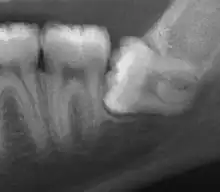

| Impacted wisdom tooth with a horizontal orientation | |

An ectopic tooth, also known as an impacted tooth, is a tooth that develops in an abnormal position and fails to erupt into its normal location in the oral cavity. [1] [2] Ectopic teeth can cause a variety of symptoms, such as pain, swelling, and infection, and they can lead to more serious complications if left untreated.

Diagnosis of ectopic teeth typically involves a comprehensive dental examination, including X-rays and other imaging tests. Treatment options for ectopic teeth depend on the location and severity of the condition, as well as the age and overall health of the patient. In some cases, observation and monitoring may be sufficient, while in other cases, surgical intervention may be necessary to remove the ectopic tooth and prevent further complications.[5]